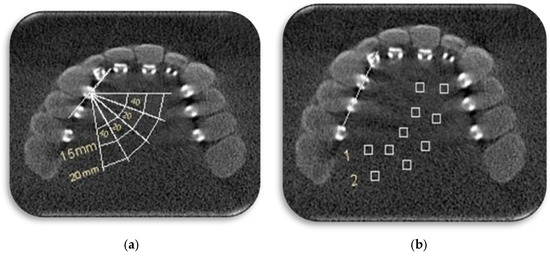

2.3. Quantitative Analysis of CBCT Images